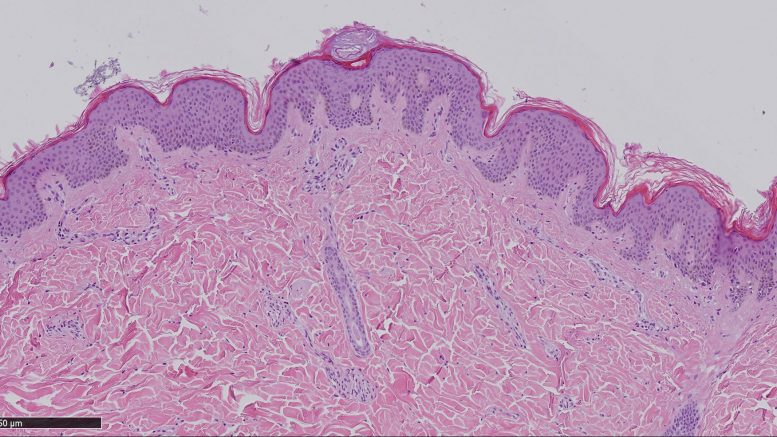

A Sassari, nella struttura di Anatomia Patologica nel 2018 sono stati diagnosticati 67 melanomi infiltranti, quando cioè la membrana basale dell’epidermide è superata ed è infiltrato il derma a vari livelli di profondità, e 30 in situ, cioè melanomi non invasivi contenuti nella membrana basale dell’epidermide. Dai dati a disposizione della struttura sassarese, la sopravvivenza a 5 anni è descritta con un range variabile nelle diverse realtà dal 75 per cento a circa il 90 per cento.